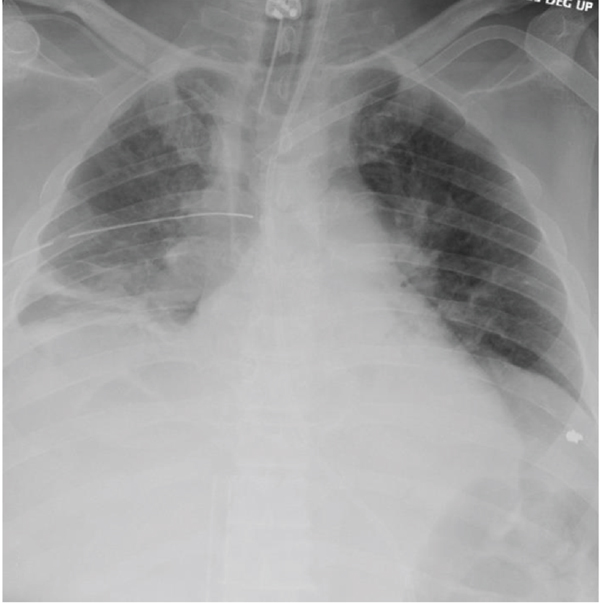

This patient is a 58-year-old man with a history of schizoaffective disorder who presented to the emergency department in October 2020 after he jumped from a third-story window. On arrival to the emergency department, he was noted to have a GCS of 3 with rightward gaze deviation and absent right-sided breath sounds. He was hypoxic and hypotensive with a negative FAST exam. Shortly into his evaluation, he lost palpable pulses and CPR was initiated. An ET tube, femoral cordis, and right chest tube were placed. Return of spontaneous circulation was rapidly achieved, although his blood pressure remained labile. Massive transfusion protocol was initiated for presumed hypovolemic shock. His hemodynamics improved, and he was taken for imaging which revealed an unstable three column fracture of the C7 vertebral body, small bilateral anterior pneumothoraces, a right retroperitoneal hematoma extending along the iliopsoas muscle with active extravasation, and significant osseous injury including displaced bilateral pubic rami fractures, right sacroiliac fracture with joint space widening, a shattered right scapula, and bilateral rib fractures with an underlying right pulmonary contusion (Figure 1). Laboratory evaluation was notable for a negative COVID-19 nucleic amplification assay. He was taken to interventional radiology and underwent embolization of bilateral hypogastric arteries as well as the right L2 and L3 lumbar arteries. Postprocedure, he was taken to the ICU for further management.